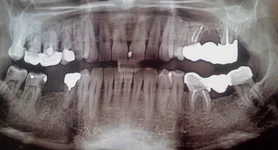

Здравствуйте уважаемые стоматологи форума!

Очень бы хотелось узнать Ваше мнение о такой ситуации. У мужа зуб №5 справа нижний - коронковая часть зуба сверху покрыта металлическим вкладышем (типа пломбы на всю жевательную поверхность зуба). Над зубом трудились два разных врача в разное время. Второй врач не смог пробить канал. Так и запломбировал зуб, наложив металл. вкладыш сверху.

Теперь стоят такие вопросы:

1) Можно ли (и стоит ли) пробить канал , пролечить его и кисту под зубом?

2) Можно ли ставить мост на №5 и №7?

3) Нужно ли удалять этот зуб?

Проблема в том, что раньше надежда была, что эту пятёрку пролечат и на нее можно будет опереть мост (на №7 и №5). мост на три зуба (где один средний удалён).

4) можно ли ставить мост в данной ситуации, если этот №5 удалить, а мост на 4 зуба, где два средних удалены? Насколько прочна будет эта конструкция?

5) Есть ли ещё зубы, которые подлежат удалению, или их можно пролечить?

Или вы можете предложить какие-то другие варианты решения?

Спасибо за ответы!

- Извлечь вкладку не просто, но такую как на снимке - возможно. Чтобы лечить зуб вкладку надо извлекать обязательно.

- Пока доктор не попробует пройти канал нельзя сказать можно вылечить зуб или нет. Но доктор нужен опытный, тогда есть шансы.

- Кисты в зубе нет. Но воспаление есть. Если удастся хорошо запломбировать канал, то мост делать можно.

- Еще требуют лечения зубы на верхней челюсти справа: 8, 7, 6, 5

- Извлечь вкладку не просто, но такую как на снимке - возможно. Чтобы лечить зуб вкладку надо извлекать обязательно.

- Пока доктор не попробует пройти канал нельзя сказать можно вылечить зуб или нет. Но доктор нужен опытный, тогда есть шансы.

- Кисты в зубе нет. Но воспаление есть. Если удастся хорошо запломбировать канал, то мост делать можно.

- Еще требуют лечения зубы на верхней челюсти справа: 8, 7, 6, 5

1) Вы говорите, что в зубе №5 кисты нет - под корнем? А есть ещё и затемнение справа по длине корня, (то есть не под верхушкой корня). Это тоже воспаление?

2) Вы считаете, что терапевтическим путём можно побороться за зуб, правильно я поняла? Пломбировка канала, его пролечивание может дать результат и для этого "бокового" воспаления?

3) Сколько приблизительно может продлиться такое терапевтическое лечение канала? Приблизительная стоимость такого решения?

4) Было предложение от стоматолога идти хирургическим путём сделать резекцию верхушки зуба наискось, удалив оба воспаления (затемнения) под верхушкой и сбоку. Но тогда от зуба ничего не остаётся, и он ненадёжен будет как опорный для моста. Вроде бы нет никаких гарантий касательно надёжности такого зуба. (не хочется, конечно, терять зуб).